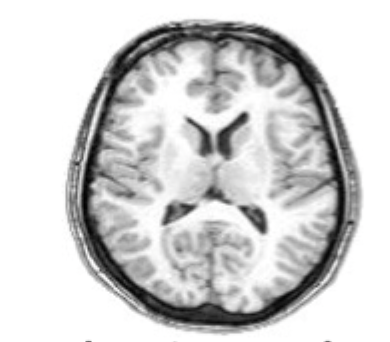

what slice of brain is this?

horizontal slice

How does gross anatomy differ from brain scans?

Gross anatomy refers to large-scale structures visible to the naked eye (e.g., gyri, sulci, lobes), while brain scans visualize these structures and functional activity using imaging techniques like MRI or CT

What is an important consideration when interpreting brain scans?

Left and right sides are reversed in images; structures on the left of the image correspond to the right hemisphere